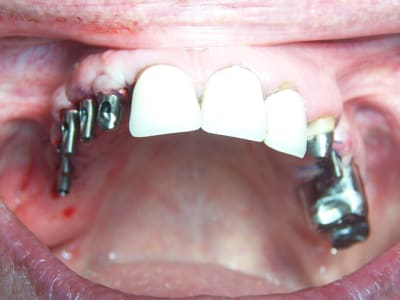

juilliet 2009 bridges provisoires sur ANKYLOS mise en charge immédiate sans scellement.

Chirurgie à COUFOULEUX, préparation prothétique et dispositif de forage à MONTASTRUC LA CONSEILLERE, dans notre belle campagne de France.